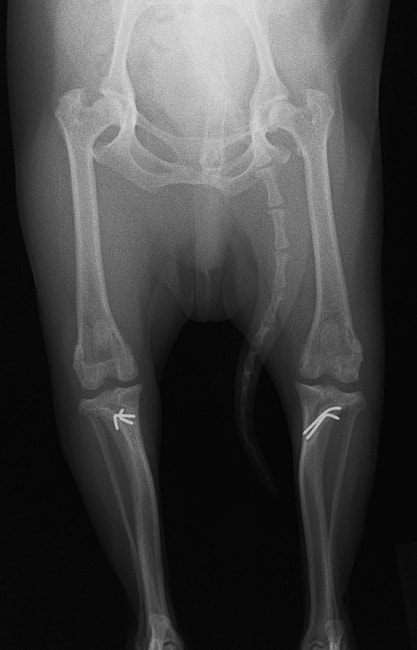

■ 症例24 キャバリア 7か月

左右膝蓋骨内方脱臼(左:グレードⅣ 右:グレードⅢ)

以前から左右後肢の跛行が認められ、整形外科学的検査・レントゲン検査により左右の膝蓋骨脱臼が認められた。症状が重度である左膝の膝蓋骨脱臼整復術を行った。外科手技は縫工筋及び内側広筋の解放、脛骨粗面の外側転位、滑車ブロック形造溝術、内外側関節方の縫縮を実施した。術後一か月時点で、左の膝蓋骨は安定しており経過は良好である。

本症例は成長期における重度の膝蓋骨脱臼であり、術後の再発の可能性もあるため、経過をしっかりと観察していく必要がある。また、今回手術を実施していない右膝に関しても経過を観察し、手術を検討していくこととする。